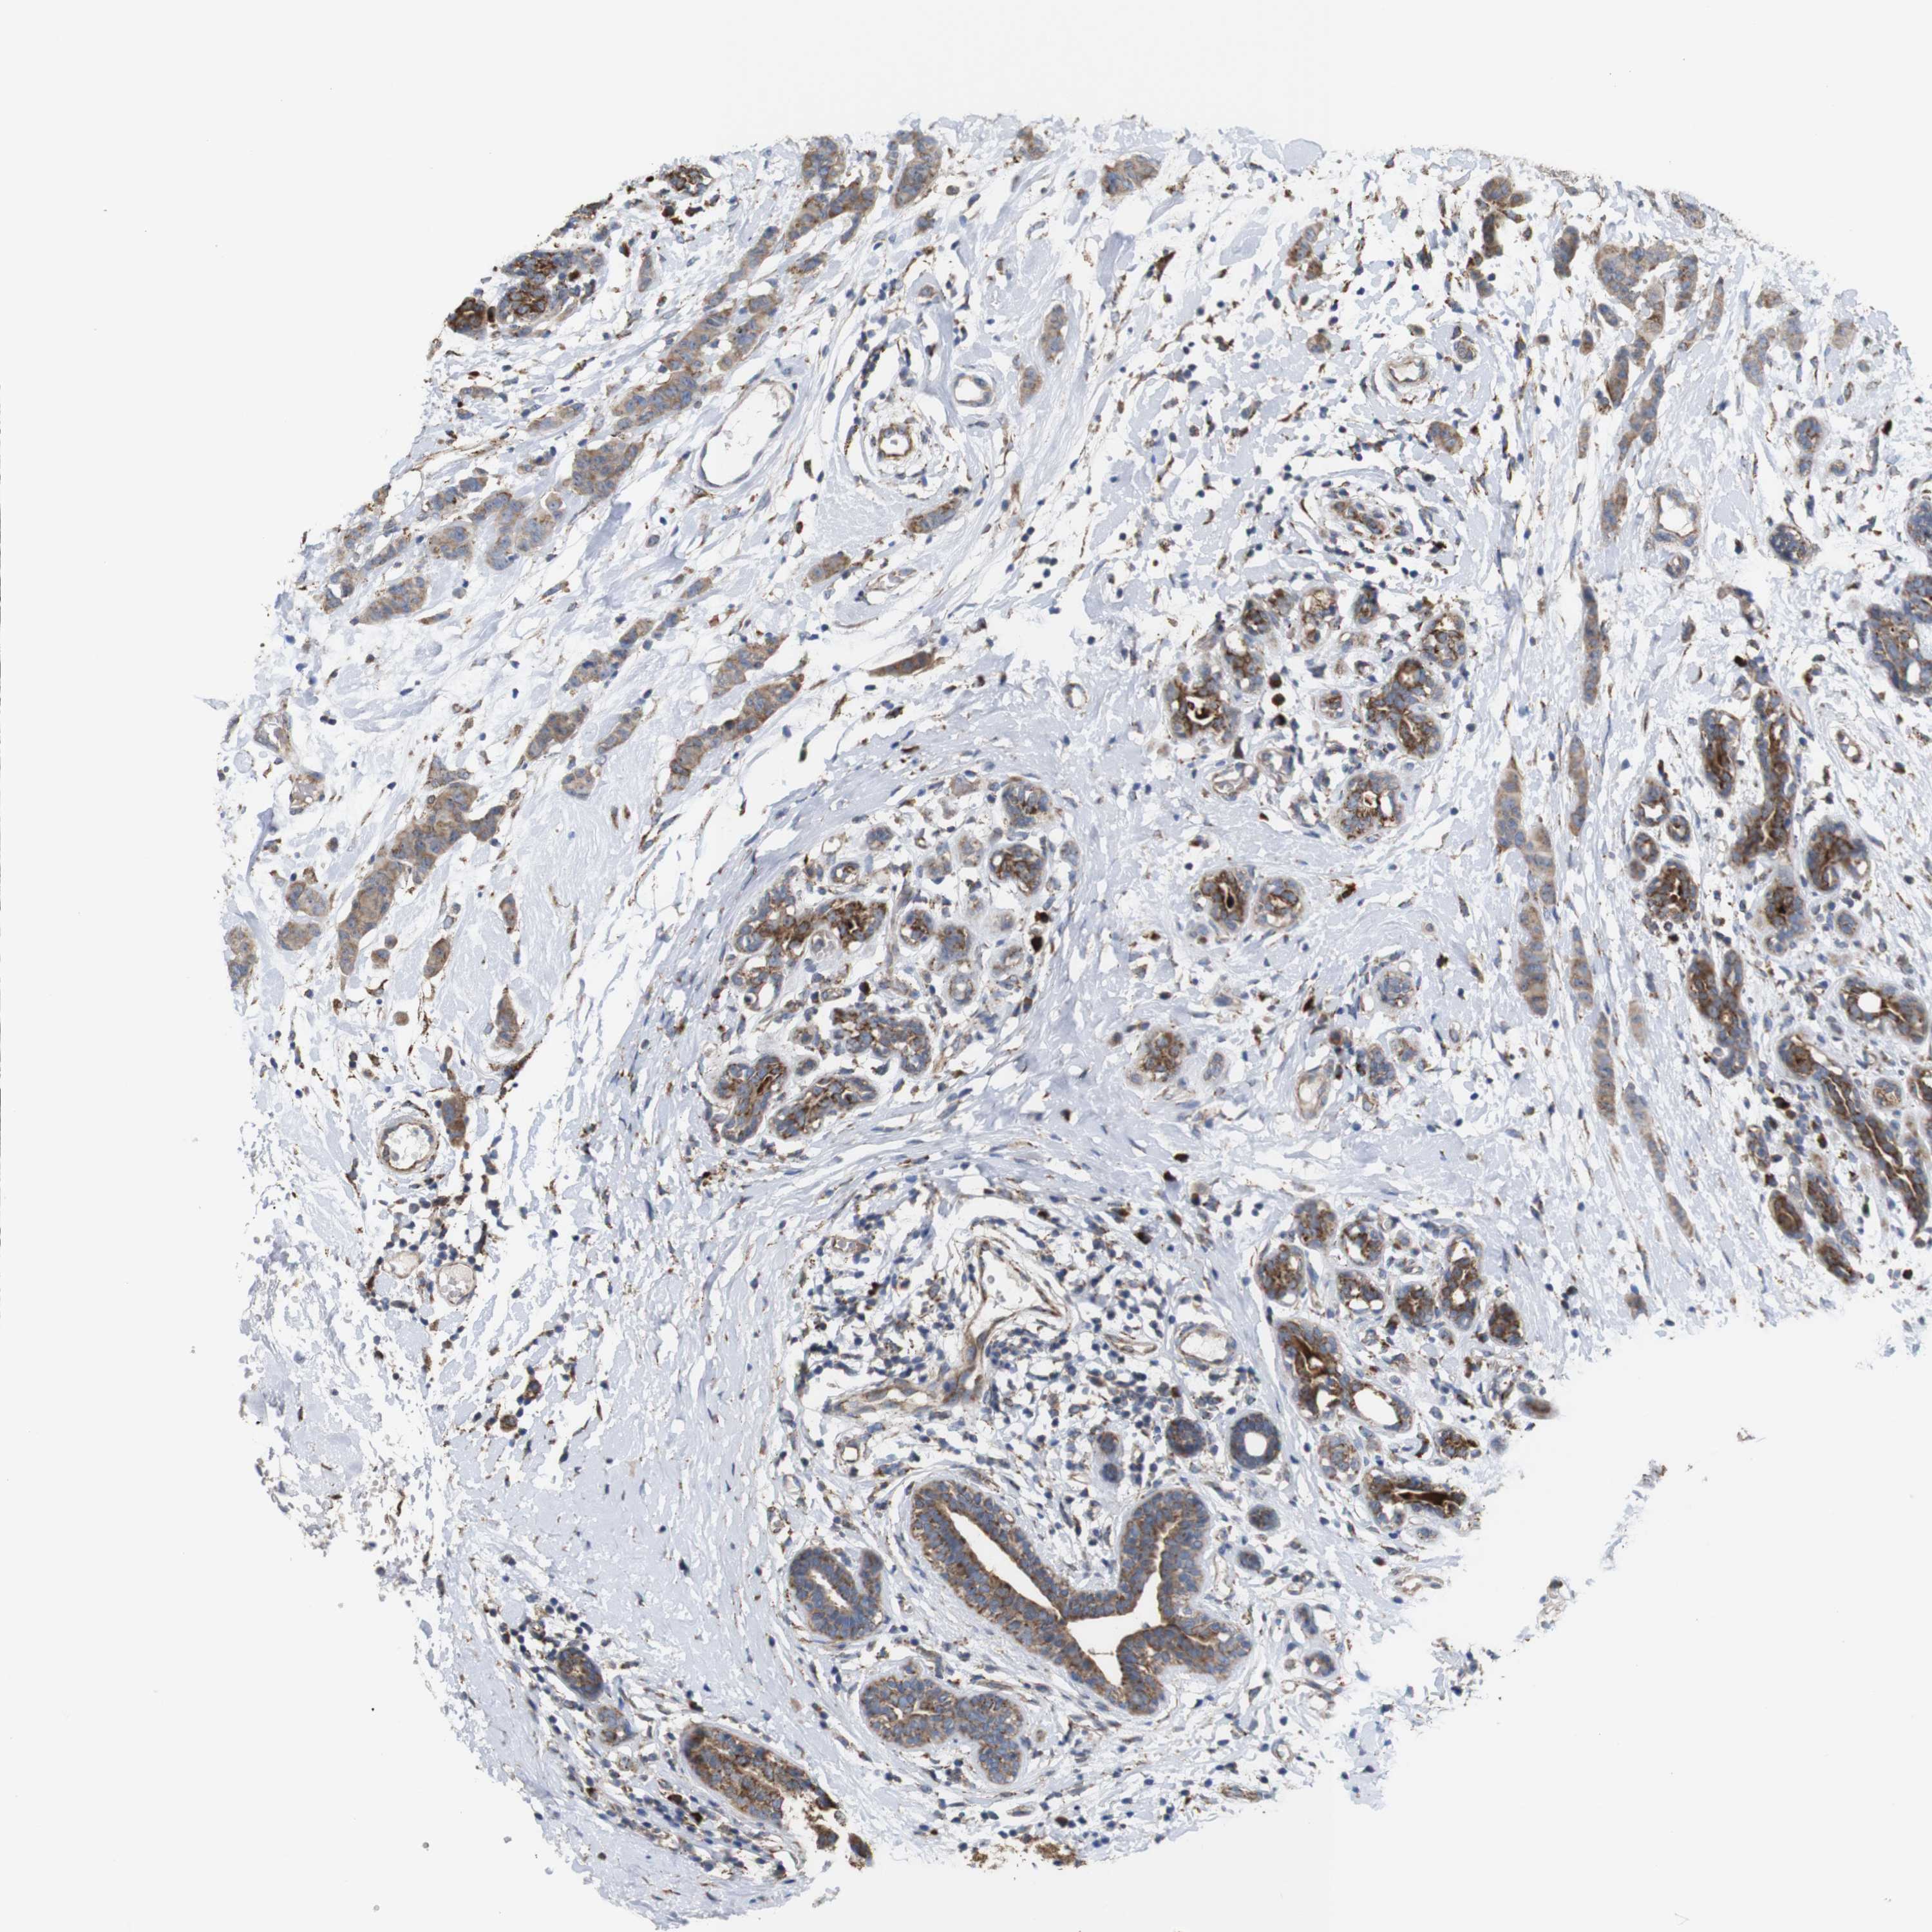

CANCER BREAST CANCER Show tissue menu

BRCA TCGA BRCA VALIDATION PROTEIN EXPRESSION